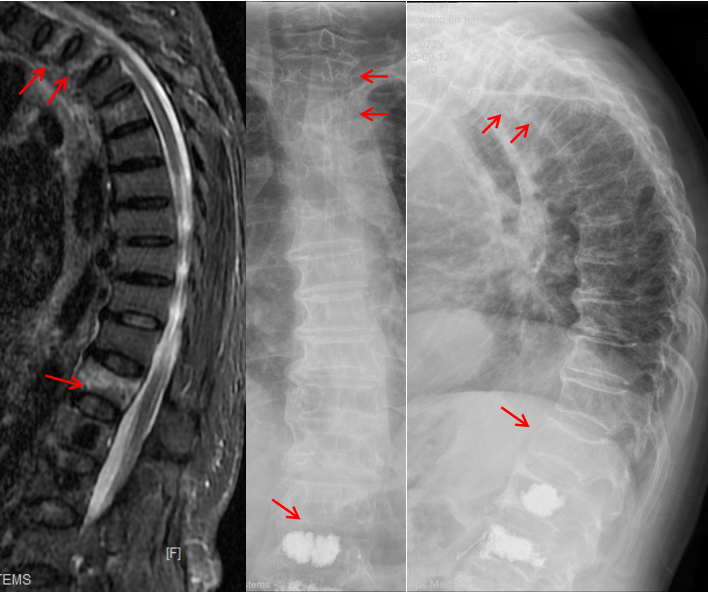

王阿姨的病情,从一开始就牵动着所有人的心。摔倒后,她随即出现胸部、肩背及腰部的剧烈疼痛,哪怕轻微咳嗽、翻身,疼痛都会急剧加剧,甚至连正常呼吸都变得困难。家人紧急将她送往北京积水潭医院贵州医院,经胸腰椎X线与核磁共振检查后,确诊其为胸2、胸3及胸12多发胸腰椎椎体压缩性骨折(图1),其中胸2、3、12椎体骨髓水肿明显,为导致她此次疼痛的“罪魁祸首”。

在C型X线及Dyla CT的实时精准引导下,穿刺针精准抵达胸2、3 椎体。团队随即通过穿刺针缓慢注入骨水泥,在C型X线实时监测下,骨水泥均匀填充至病变椎体中。整个手术历时40分钟,术中出血量不足5ml,术后即刻 X线显示:骨水泥分布均匀,无渗漏,周围脏器与神经未受任何损伤 —— 这场椎体成形术“相对禁区” 的攻坚战,以完美结果宣告成功。